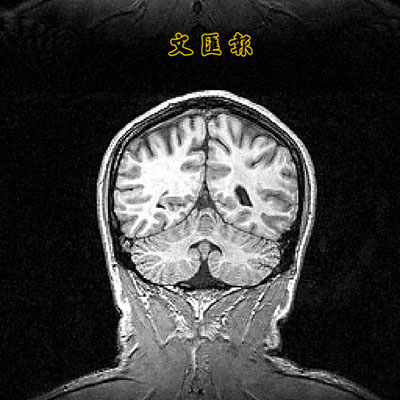

■左腦在噪音環境下活動較活躍。資料圖片

加拿大、日本和德國的研究人員通過研究發現,人類的左腦能夠從亂七八糟的刺耳聲音中過濾噪音,挑出自己想聽到的聲音。

日本生理學研究所研究員垣木表示:「在日常生活中,我們總是同時接觸幾種噪音,不得不從背景噪音中挑出重要的信號,比如語音。我們發現在人聲嘈雜的環境中,大腦左半球通常在聽覺處理方面佔著主導地位。」

眾所周知,語言信號是在左腦得到處理的。研究員通過這項研究,可以進一步了解人腦如何能夠把注意力集中到想要的具體聲音上,以及如何能夠處理這些聲音。

科學家安排志願參加測試者接觸不同的聲音和背景聲音組合,以便他們利用神經影像學技術觀測這些測試者的神經機制。

這些參與研究的科學研究員指出:「測試聲音傳給左耳或者右耳,而同時把製造的噪音傳給同一隻耳朵或者另一隻耳朵。我們通過監測大腦對這些不同聲音組合的反應後發現,要在人聲嘈雜的環境中處理聲音,相關的大部分神經活動所在區域是大腦左半球。」 (念持)